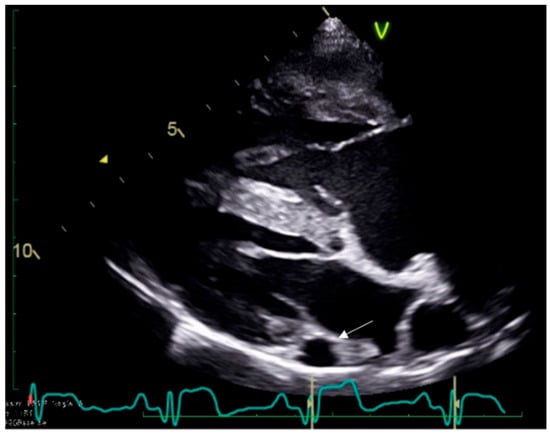

2.3. Case 3